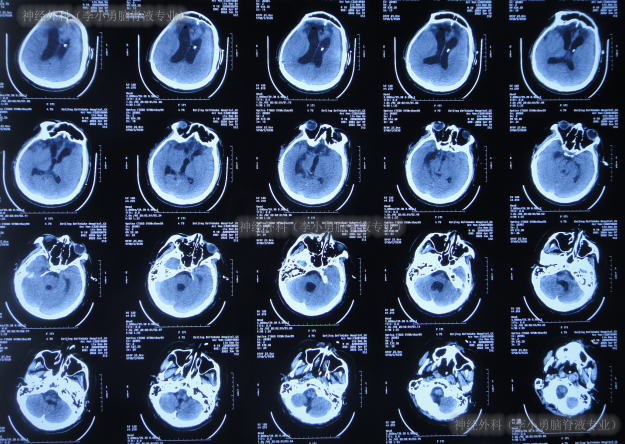

入院时头颅CT示颅骨修补术后,脑分流术后仍脑积水(图-17)。

图-17:2022年6月9日头颅CT

入院后次日即2022年6月10日,拔除了原脑室腹腔分流管+脑室外引流术(图-18)。

图-18:2022年6月10日头颅CT